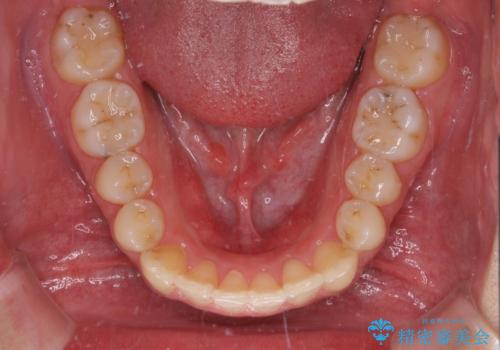

狭い歯列と前歯のデコボコ インビザラインによる矯正治療

- 上下前歯のデコボコを気にして来院された患者様です。

インビザラインによる上下歯列の拡大と、IPR(歯と歯の間を削る)にるスペースの獲得により、前歯のデコボコと狭い歯列を改善することとしました。

比較的軽度な歯列不正であったため、治療期間はそれほど長くはならないと予想されました。

しかしながら、あまりしっかりとマウスピースを装着していなかったため、思いの外期間が長引いてしまいました。

また、仕上がりの歯列にも若干の叢生が残ってしまいました。